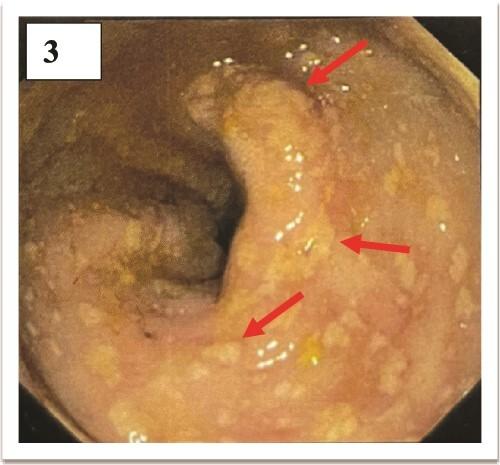

Enteric fever is one of the important causes of tropical fever with a prevalence of 11-21 million cases worldwide annually. It encompasses both typhoid and paratyphoid fever. Typhi is the causative organism for typhoid fever, manifesting as an uncomplicated febrile illness to life-threatening sepsis with multiorgan dysfunction. It is complicated by neuropsychiatric manifestation (2%-40%), gastrointestinal bleeding (10%), and intestinal perforation (1%-3%). Hemophagocytic Lymphohistiocytosis (HLH) is a rare complication of typhoid fever. Herein we report the case of a 24-year-old male from North-Eastern India, presenting with spikes of fever, altered behavior, a generalized rash, haematochezia, and hemophagocytes on bone marrow examination due to hemophagocytic lymphohistiocytosis secondary to complicated typhoid fever.

肠热症是热带发热的重要病因之一,全球每年患病率为1100万至2100万例。它包括伤寒和副伤寒热。伤寒杆菌是伤寒热的病原体,表现为从单纯发热性疾病到伴有多器官功能障碍的危及生命的败血症。其并发症包括神经精神表现(2% - 40%)、胃肠道出血(10%)和肠穿孔(1% - 3%)。噬血细胞性淋巴组织细胞增生症(HLH)是伤寒热的一种罕见并发症。在此,我们报告一例来自印度东北部的24岁男性病例,该患者因复杂型伤寒热继发噬血细胞性淋巴组织细胞增生症,出现发热高峰、行为改变、全身性皮疹、便血以及骨髓检查发现噬血细胞。